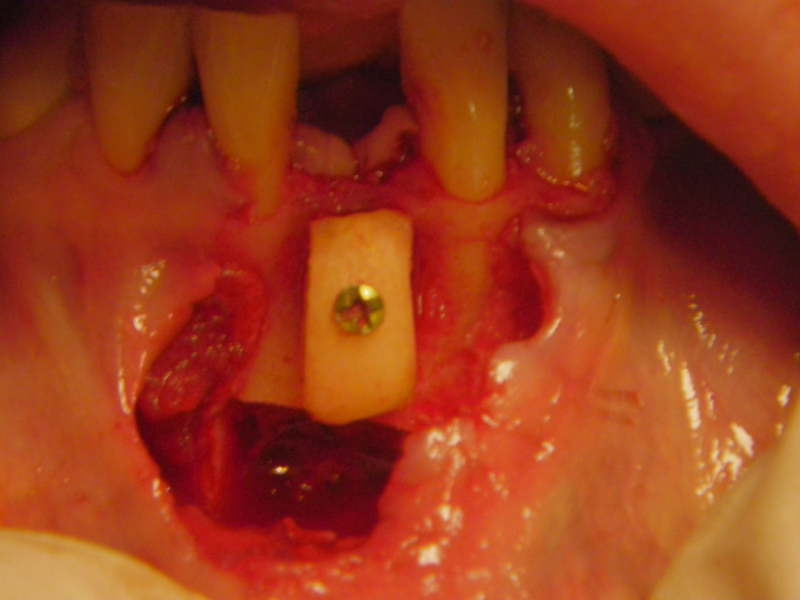

- Stage I: Implant placement/Sealing Screw

- Bone grafting – autogeneous, alogenic, xenogenic

- Blockgraft

- Fixation (plate, screws, wire)